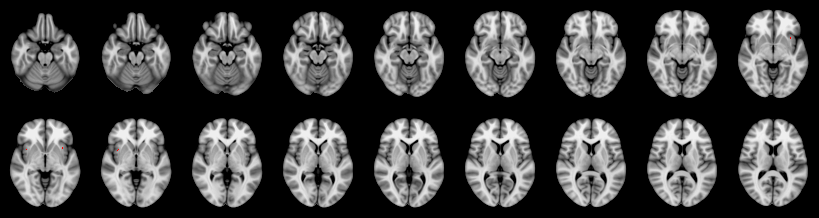

Hotelling T2: